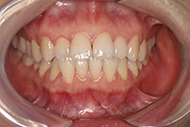

2018年7月 现在佩戴第五幅牙套,非常舒适

转眼3个月了,戴的牙套没有任何感觉,跟朋友说话,吃饭其实都不影响的,不过就是吃东西的时候要摘下来,家里的小朋友逐渐懂事,会好奇透明的东西是什么,不过身为一名医护的职业反射,对小朋友牙齿这块还是注意的~今天看了牙,顺便带小朋友检查一下牙齿,然后再补过一个儿童节~

接着说复诊,医生说和3D动画的步骤一样,问我有什么不适没有,就是吃东西的时候要摘下来,其他的也没有影响我的日常工作~